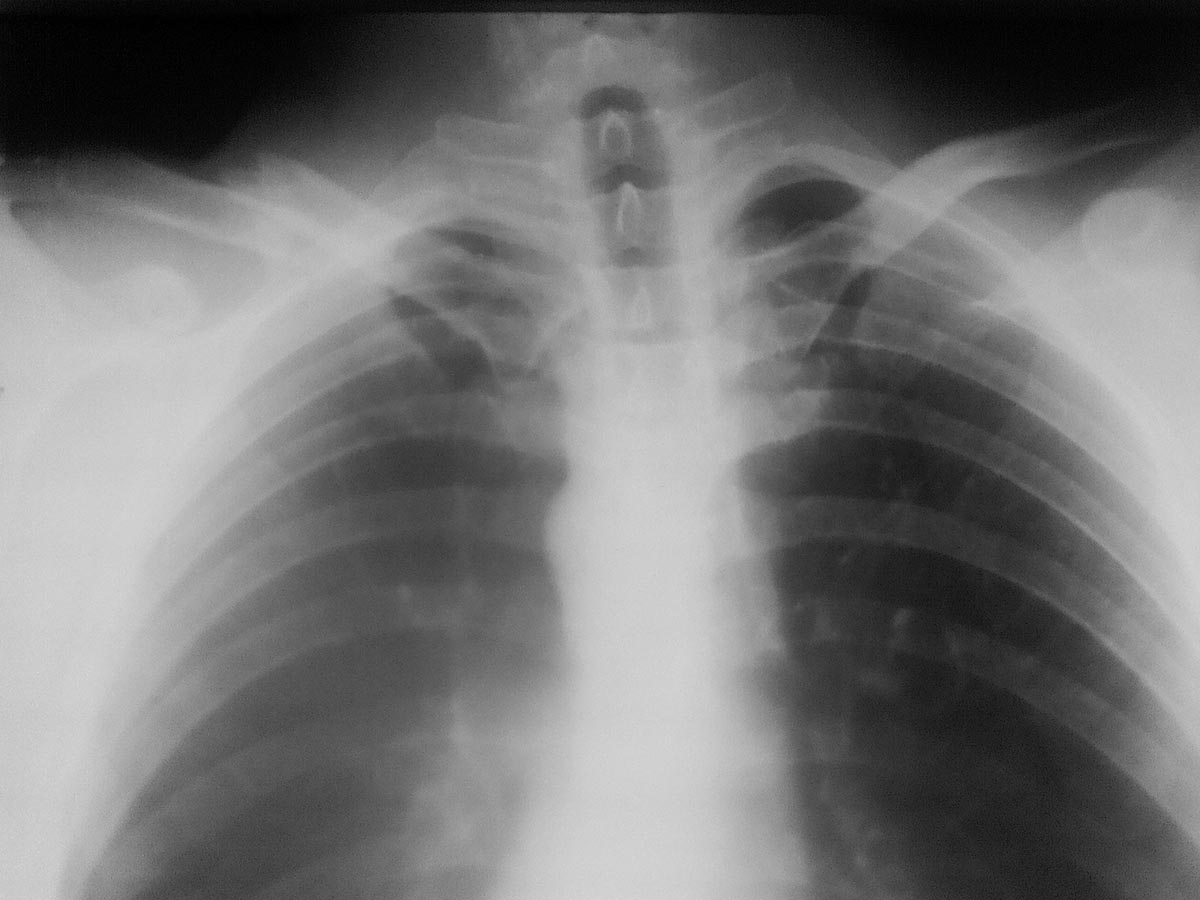

Мужчина, 35 лет, 23.11.15 получил закрытый оскольчатый перелом левой

ключицы в результате падения на руку с высоты роста. 26.11.15 выполнена

операция: Открытая репозиция, интрамедуллярный остеосинтез штифтом

Богданова, промежуточные осколки фиксированы на место лавсановыми

нитями. Остеосинтез выполнил по классической методике: через доступ

длинной 5 см экономно скелетировал отломки, рассверлил сверлом 3.2 мм

каналы в дистальном и проксимальном отломках, подобрал соответствующего

диаметра стержень Богданова, который антеградно ввбил в репонированные

отломки,промежуточные осколки фиксировал лигатурами к месту перелома.

Смущает одно, что изначально стержень не изгибал под S-образную кривизну

ключицы, а на R-графии после остеосинтеза стержень деформировался под

изгиб ключицы.

Изначально планировал стержень расположить "широкой" частью фронтально,

но не вышло.